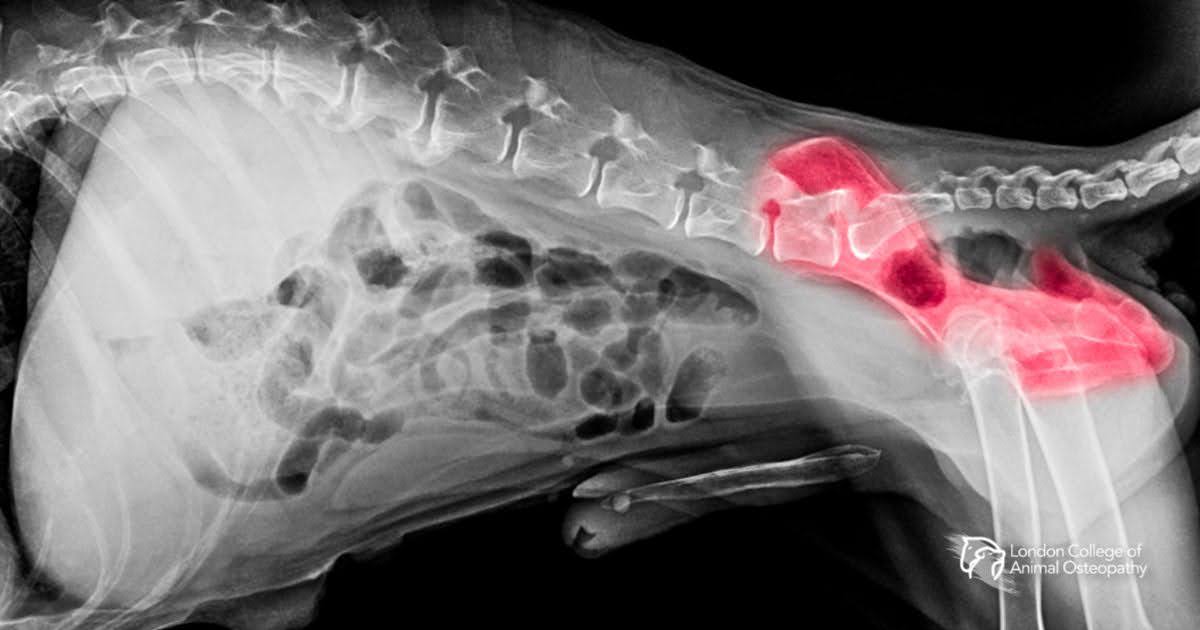

Hip dysplasia in dogs (often called CHD, or canine hip dysplasia) is a developmental joint condition in which the femoral head and the acetabulum don’t form a stable, congruent ball-and-socket joint. Over time, that laxity causes abnormal wear, inflammation, and osteoarthritis. Clinical signs range from subtle exercise intolerance to obvious lameness. Early identification and a tailored plan make the biggest difference to long-term comfort and mobility.

Early diagnosis is vital. Vets use physical exams, gait assessment, and imaging (X-rays or CT) to confirm the condition.

- Confirm diagnosis through veterinary imaging (X-rays, PennHIP, or OFA screening)